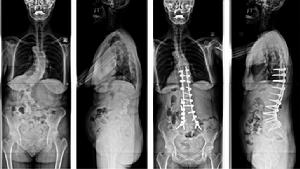

圖2-2:特發性脊柱側凸手術前後對比:男,22歲,術前主胸彎62°,術後矯正為23°

圖7-1和7-2退變性脊柱側凸術前正側位;圖7-3和圖7-4術後固定情況